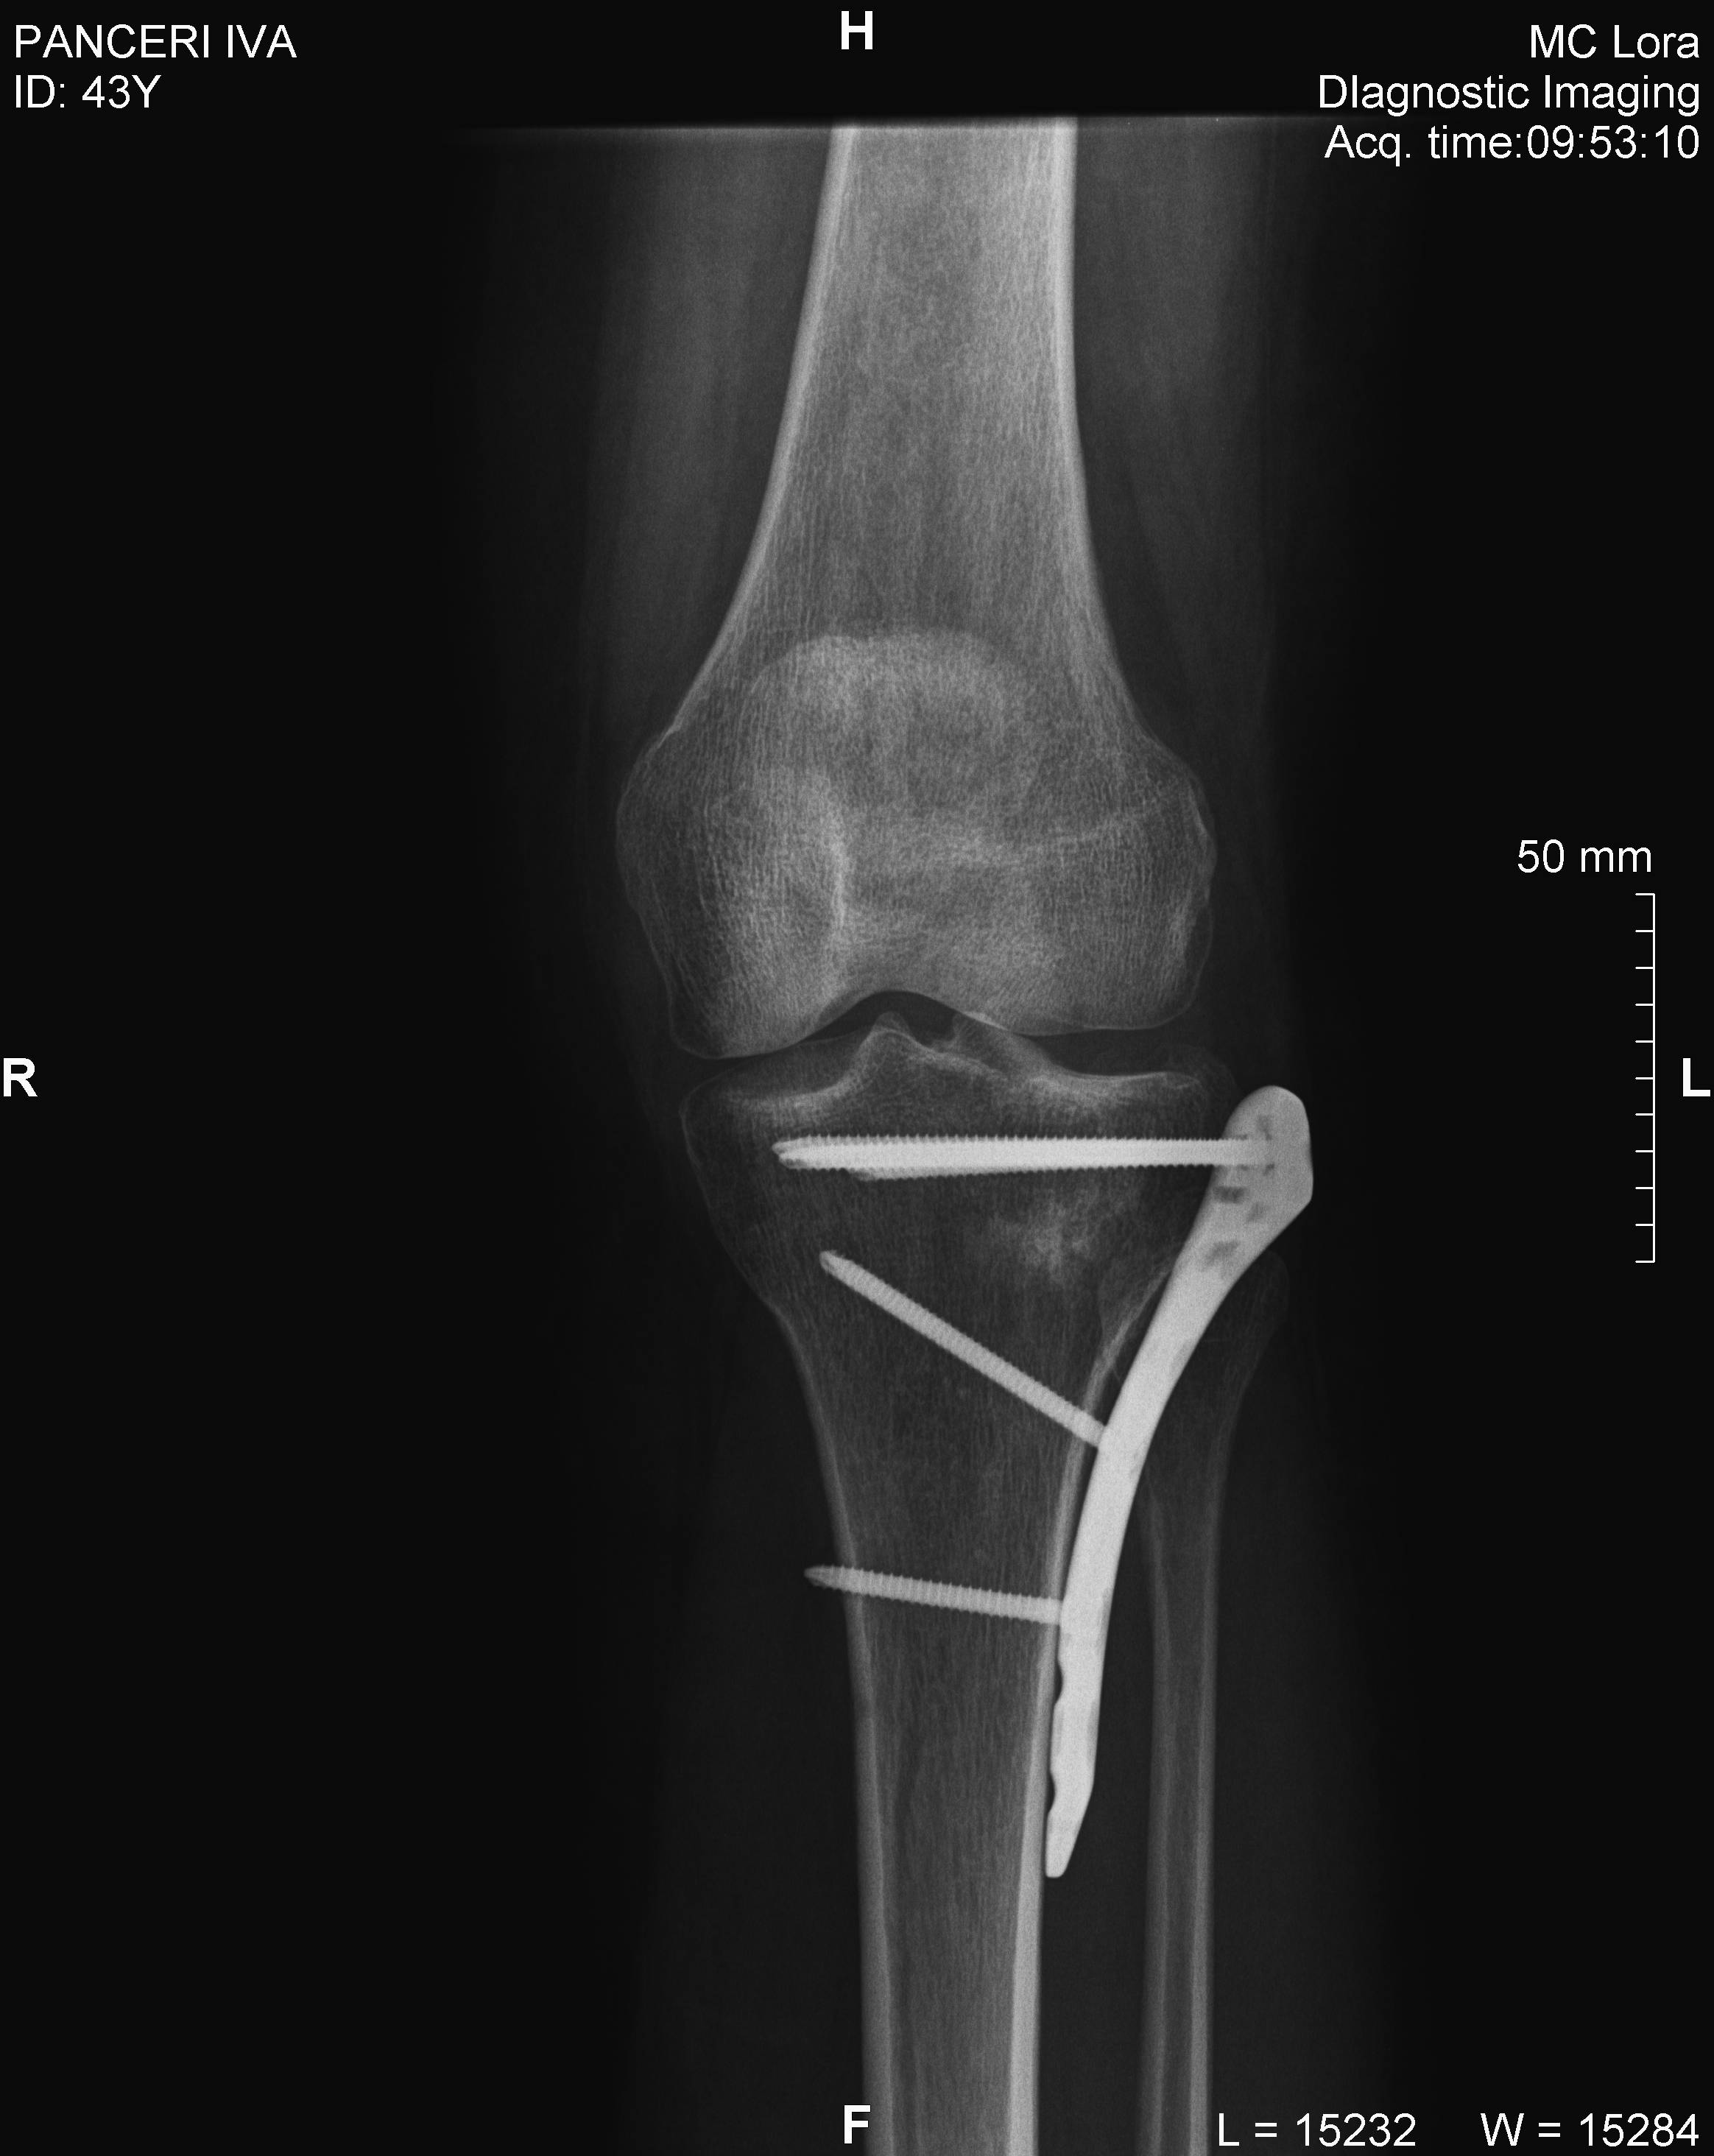

a seguito di un incidente avvenuto quattro mesi fa sono stata operata al piatto tibiale con impianto di osso sintetico e l'applicazione di osteosintesi con 6 viti. Poiche' durante l'incidente mi trovavo all'estero, l'intervento e' stato eseguito a Sofia. Adesso, dopo quattro mesi inizio a camminare ma chiedo un parere, allegando il file conuna radiografia prima dell'intervento e una fatta due giorni fa. A vostro parere era necessario un intervento simile e se si, in base all'ultima lastra vi sembra che sia tutto a posto?

Panzeri_11.11.16.jpg